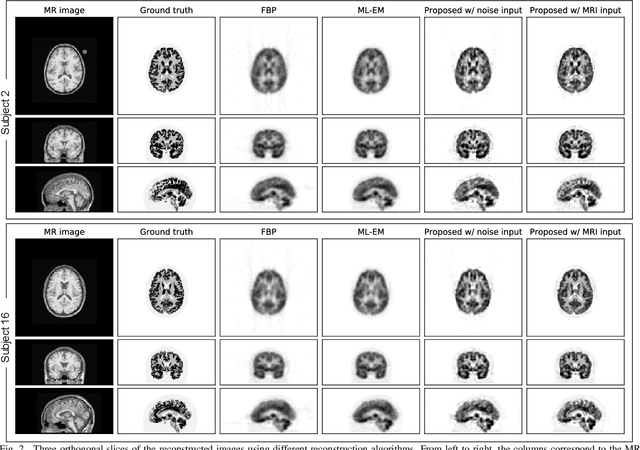

Abstract:Convolutional neural networks (CNNs) have recently achieved remarkable performance in positron emission tomography (PET) image reconstruction. In particular, CNN-based direct PET image reconstruction, which directly generates the reconstructed image from the sinogram, has potential applicability to PET image enhancements because it does not require image reconstruction algorithms, which often produce some artifacts. However, these deep learning-based, direct PET image reconstruction algorithms have the disadvantage that they require a large number of high-quality training datasets. In this study, we propose an unsupervised direct PET image reconstruction method that incorporates a deep image prior framework. Our proposed method incorporates a forward projection model with a loss function to achieve unsupervised direct PET image reconstruction from sinograms. To compare our proposed direct reconstruction method with the filtered back projection (FBP) and maximum likelihood expectation maximization (ML-EM) algorithms, we evaluated using Monte Carlo simulation data of brain [$^{18}$F]FDG PET scans. The results demonstrate that our proposed direct reconstruction quantitatively and qualitatively outperforms the FBP and ML-EM algorithms with respect to peak signal-to-noise ratio and structural similarity index.